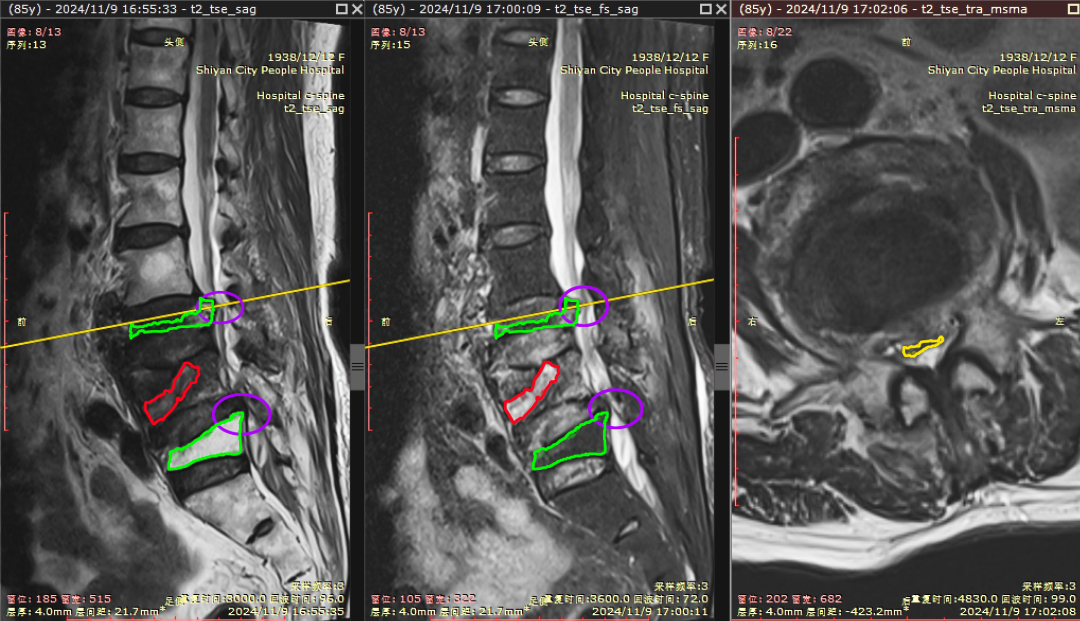

• 端水閃著腰,一查竟腰椎骨折!十堰人醫(yī):這類人群要警惕

端水閃著腰,一查竟腰椎骨折!十堰人醫(yī):這類人群要警惕

今日房縣網(wǎng)訊?“我就端了盆水,也沒有跌倒,怎么就骨折了呢?”85歲的張奶奶百思不得其解。隨著年齡的增大,大部分老年人都患有骨質(zhì)疏松情況,嚴(yán)重時甚至打個噴嚏、咳嗽一聲都有可能造成骨折。85歲張奶奶端盆水閃著腰疼痛難忍無法行走…